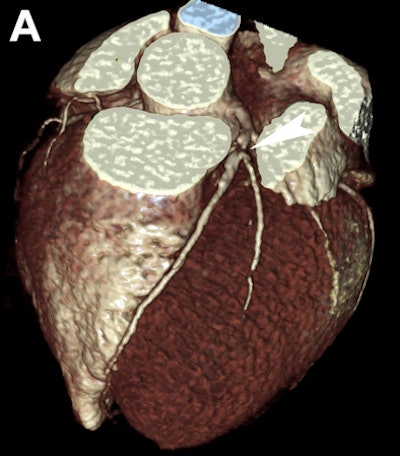

| Images are of a 42-year-old man with atypical chest pain and no significant ECG or troponin alterations. Clinical assessment was in favor of mild pericarditis. CT shows in 3D volume rendering (A) and curved multiplanar reformats (B) the presence of an obstructive atherosclerotic plaque at the proximal left anterior descending coronary artery (arrowhead). Image courtesy of Dr. Filippo Cademartiri, PhD. |